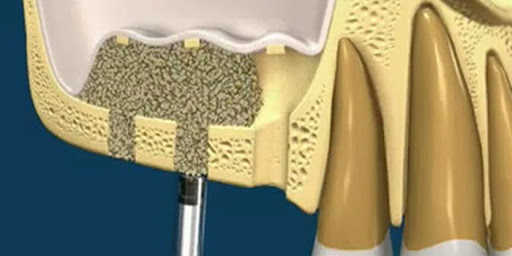

Kemik yetersizliğinin olduğu bölgelere kemik greftlerinin yerleştirilerek desteğin sağlanması.

İmplant Cerrahisi

Eksik dişlerin implantlarla tamamlanması için suni kök yerleştirme

Gerekliyse bu bölgenin implant öncesi cerrahi ile hazırlanması için kemik greftleri ve membranları ile hazırlanması.